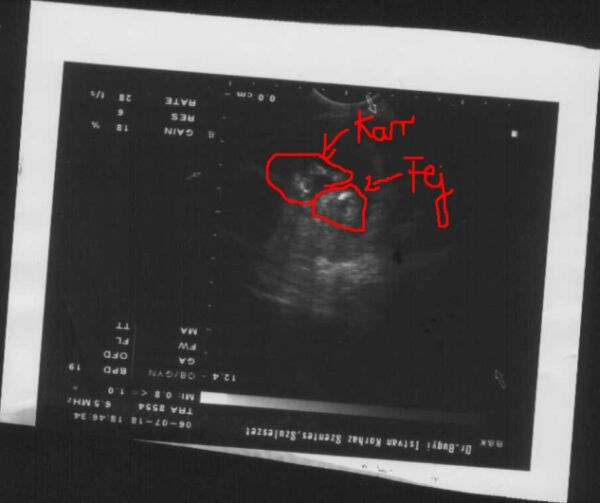

1 hete voltam UH-n. CRL: 49mm, fültől fülig 19 mm, tarkóredő 0,9 mm, 4 végtag látható, szívműködés látható, koponyacsont ép.

Megpróbálom feltenni az egyik képet. Azon csak a fej és a kar látszik, ahogy a szájánál van, mintha szopizna. A másikat apunak adtam, vigyáz rá. (Illetve anyu rakta a szívéhez, én nem mertem megnézni őt)